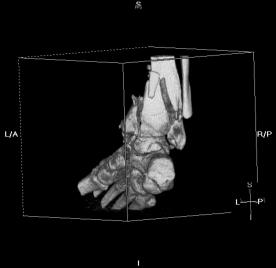

Pre-skin graft & bone infuse surgery X-Rays of the left ankle

These x-rays were taken just prior to surgery where grafts of skin (from Liam's own leg) were used to cover the open wound on Liam's left

ankle. Dr. Gottlieb also took the initiative to infuse material into the tibia gaps (shown in the front ankle view). The infused bone material

should fill in the existing bone gaps and fuse the various bone fragments, resulting in a much stronger support structure. It is hoped that the

3 cm fragment (shown in the side view) will fuse with the other tibia bones as time progresses. No immediate plan exist to modify the remaining

bone fragments / configuration.